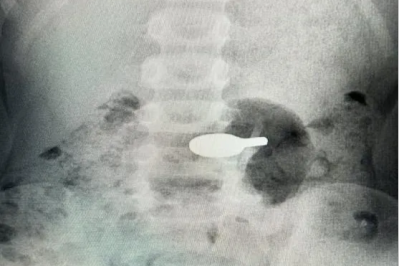

桂林医科大学第二附属医院(第二临床医学院)是桂林医科大学直属的现代化大型综合医院,邻近桂林市政府和桂林医科大学新校区(主校区),交通便利,环境优雅。医院始建于1942年,2014年更名为桂林医学院第二附属医院,2025年更名为桂林医科大学第二附属医院,占地面积82900平方米,编制床位数1200张,是一家集医疗、教学、科研、预防、康复、急救为一体的国家三级甲等综合医院,为全国百姓放心示范医院、自治区文明单位、国家药物临床试验机构、自治区首批药品临床综合评价基地。 学科齐全,锻造办院特色。医院设有53个临床、医技科室,86个专科、专病门诊,16个护理门诊,并在广西率先建立了独立的脑血管病(脑卒中)诊疗专科,桂林市首家家庭式产待一体化产房,切实提供优质高效的诊疗服务。 实力强劲,推动内涵提升。医院现有13个广西医疗卫生重点(培育)学科(呼吸与危重症医学科、感染性疾病科、心血管内科、儿科、麻醉科、重症医学科、急诊医学科、普通外科、骨科、产科、肿瘤内科、神经内科、消化内科),3个广西临床重点专科建设(培育)项目(心血管内科、风湿免疫科、泌尿外科),5个市级重点专科(麻醉科、临床药学、心血管内科、肿瘤科、肝病科(传染病方向)),是国家高级卒中中心、中国胸痛中心、中国房颤中心、全国乳腺癌规范诊疗示范中心建设单位、首批国家级神经介入建设中心、国家标准化过敏性疾病诊疗中心、广西产前诊断机构、桂林市超声诊断质量控制中心、桂林市危重孕产妇救治中心和危重新生儿救治中心、桂北地区唯一一家毒蛇咬伤救治中心。一流的专科,卓越的实力,为广大百姓健康保驾护航。近年来,医院门急诊人次、出院病人数和手术台次稳步提升,诊疗范围辐射桂北地区及邻近省市,服务人口近2000万。 创新驱动,科研平台优越。医院大力实施科教兴院战略,坚持用科研创新推动医院发展,现有国家级研究平台——国家代谢性疾病临床医学研究中心分中心,省级临床研究平台——广西糖尿病及代谢疾病临床医学研究中心,省级重点实验室——广西慢性病代谢重塑与智能医学工程重点实验室,厅级研究平台——广西糖脂代谢病重点实验室、广西高校呼吸疾病重点实验室,广西高校高水平创新团队——慢性肺部高发性疾病研究团队,以及广西博士后创新实践基地等多个科研平台。